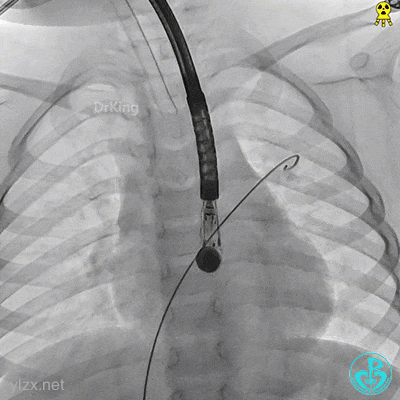

右盘展开

右盘展开,牵拉成型线使得封堵器双盘扣合住间隔。

锁定前确认

牵拉试验,封堵器骑跨于缺损两侧。

封堵器整体稳定,仅右盘随钢缆牵拉移动。